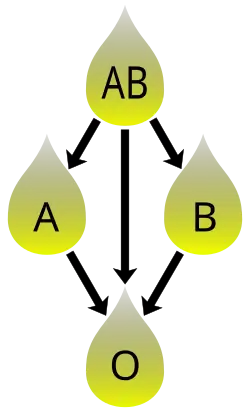

In addition to donating to the same blood group, plasma from type AB can be given to A, B, and O; plasma from types A, B, and AB can be given to O.

Blood plasma compatibility is the inverse of red blood cell compatibility.[36] Type AB plasma carries neither anti-A nor anti-B antibodies and can be transfused to individuals of any blood group; but type AB patients can only receive type AB plasma. Type O carries both antibodies, so individuals of blood group O can receive plasma from any blood group, but type O plasma can be used only by type O recipients.

For transfusions of plasma, this situation is reversed. Type O plasma, containing both anti-A and anti-B antibodies, can only be given to O recipients. The antibodies will attack the antigens of any other blood type. Conversely, AB plasma can be given to patients of any ABO blood group, because it does not contain any anti-A or anti-B antibodies.